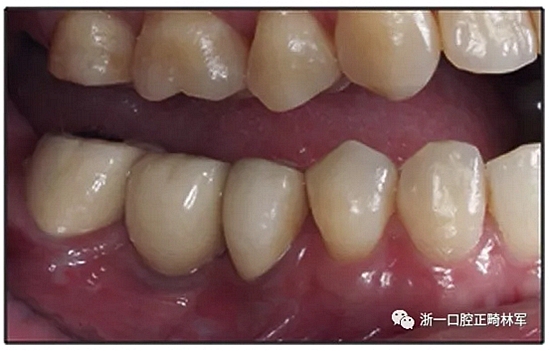

經(jīng)過32個月的活動治療后,上下牙弓排齊良好,下頜第一磨牙區(qū)的雙側(cè)牙間隙可用于種植(圖12,A和13,A)。

治療結(jié)果

該患者獲得了理想的功能和美觀。